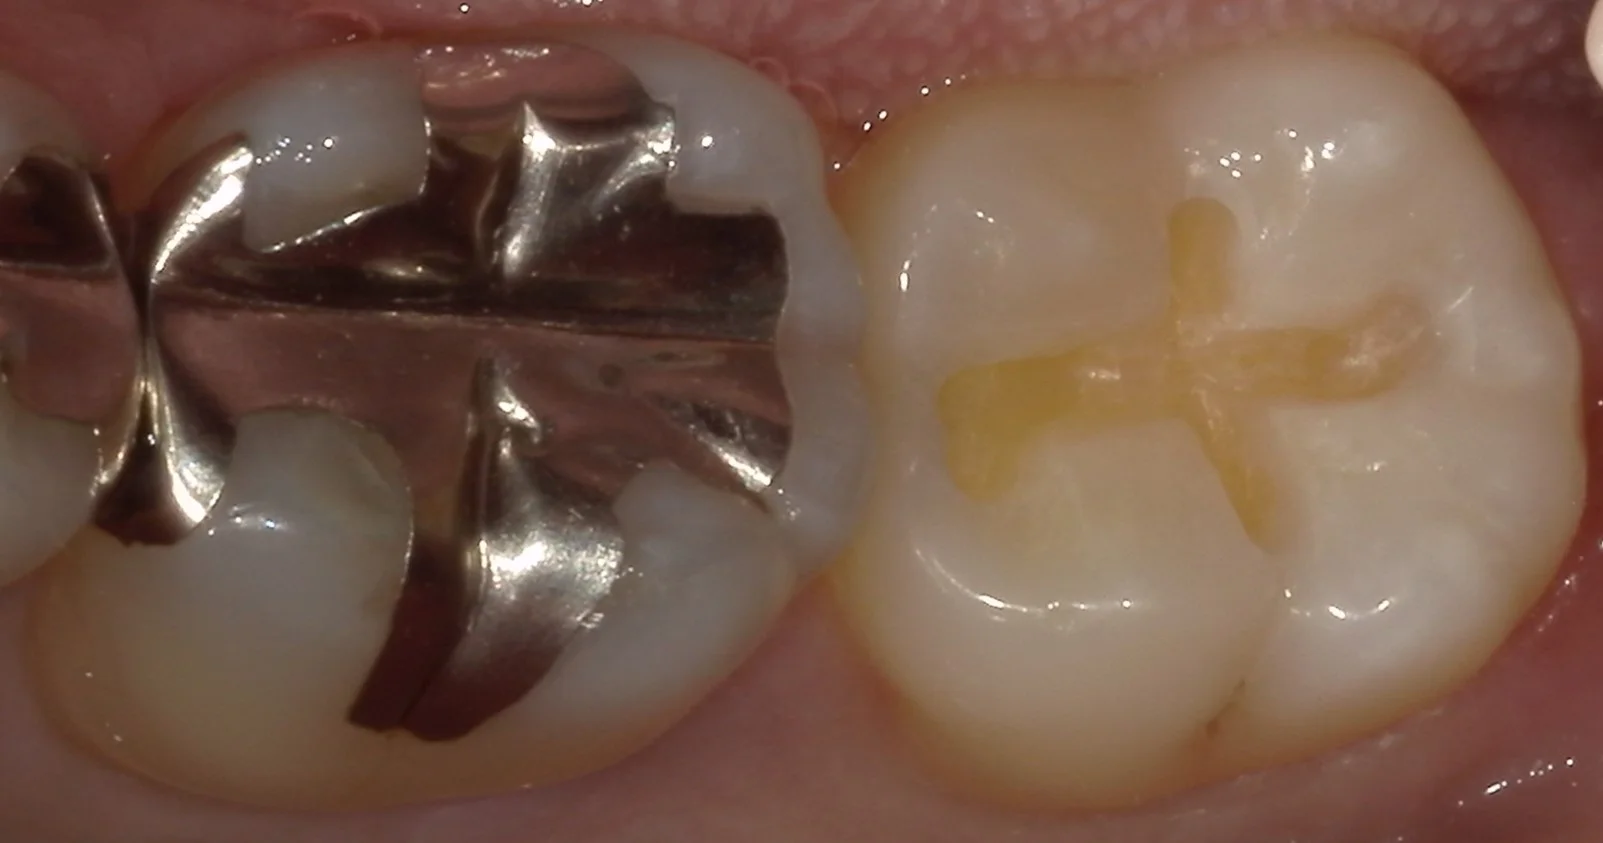

さて、そして詰め物だけ外したのがこちらです。

透けて見えていた部分はそこまで深くありませんが、画面の上下に位置する黒い部分。

ここが非常に深かったです。

そして、虫歯を取り切ったのがこちらの写真です。

綺麗に歯の色が出たのがわかるかと思います。

詰め物の治療をする際、着色部分も含めてしっかりと除去しておいた方が接着には有利に働くのがわかっていますので、無理のない範囲で除去しきるようにしています。